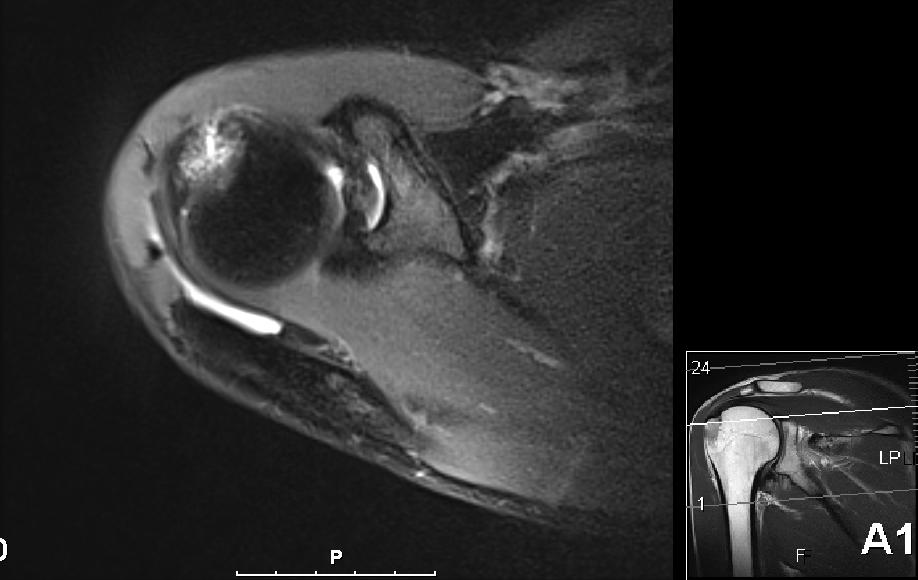

I forrige uke kom uansett svaret og resultatet var ikke akkurat helt som forventet. Nå var det riktig nok noe betennelse (aka bursitt) i skuldra som forventet men det var også et brudd i kanten på skuldra, såkalt tuberculum majos fracture på 2 x 2 cm. Så Kristian og Jørn Erik var rimelig overrasket over at jeg meldt tilbake at svømmingen gikk så bra.

Nå er det bare 6 dager til Ironman 70.3 Mallorca, og som alltid så ønsker jeg selvsagt å delta, men forstår at det kanskje ikke er det mest fornuftige. Om noen av dere har erfaringer eller gode råd/tips så tas de i mot med stor takk! Nå forstår jeg at radiolog er et eget yrke og tolking av MR-bilder krever mye erfaring og kunnskap, men jeg syntes ikke det ser såååå ille ut egentlig.

Skulderbilde

Allan - Skulder ovenfra 2

Allan - Skulder ovenfra 3